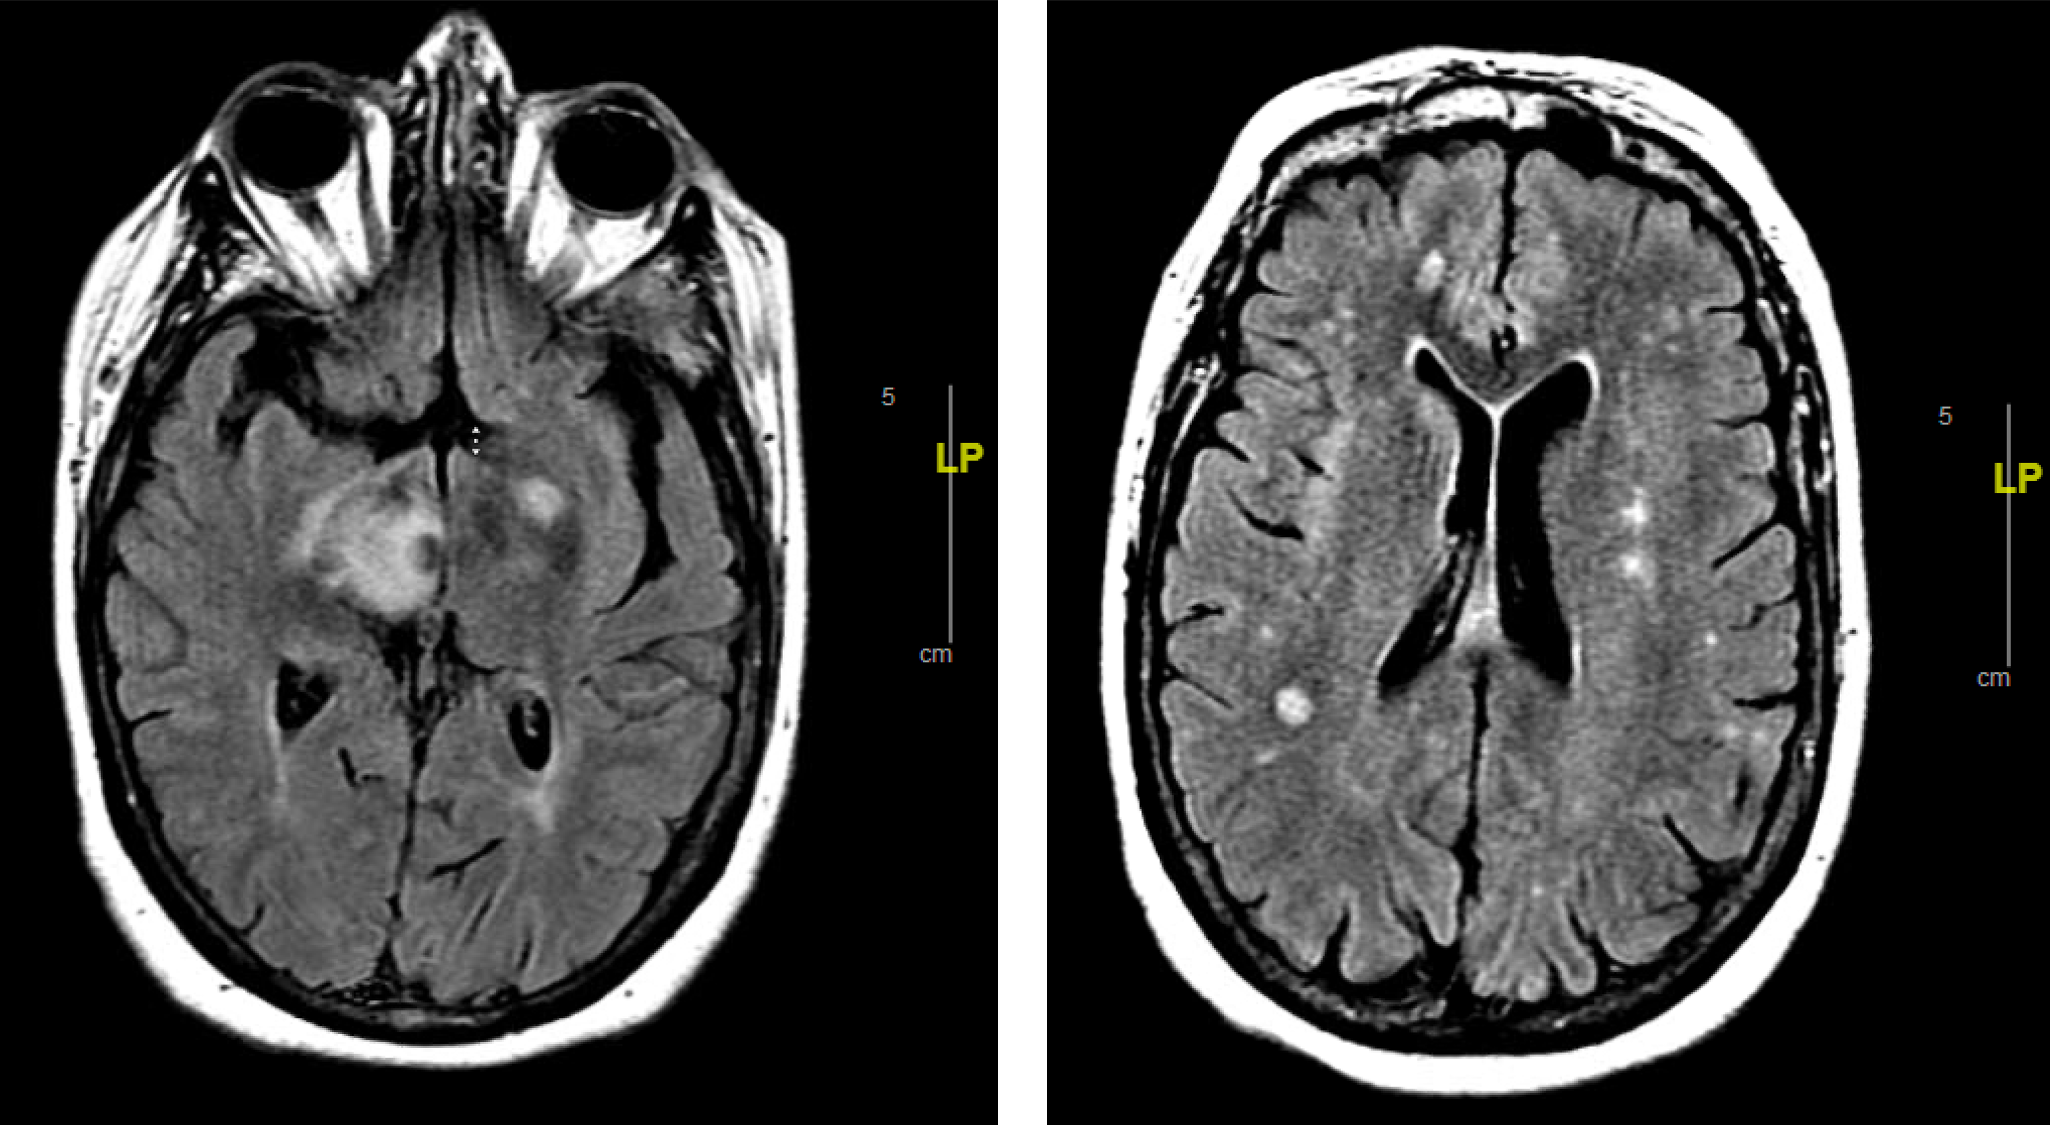

Category: CNS Infection